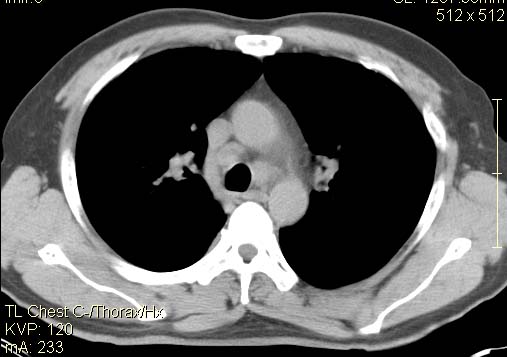

以下是引用qc80012345在2007-4-17 12:33:00的发言:[br]右肺下叶周围型肺癌伴肺门及纵隔内淋巴结转移;比较清楚。

以下是引用qingyuan在2007-4-17 14:19:00的发言:[br]右肺下叶外侧后段胸膜下区节结样病变、分叶、内可见空洞,壁厚薄不均,胸膜凹陷、肺门周围区纹理增粗、僵硬、并近似小结节样改变,肺门区软组织节结、纵膈淋巴结肿大,患者病史长、抗炎治疗无好转炎性改变基本排除,考虑:右肺下叶周围型肺癌伴纵膈及右肺门区淋巴结转移、肺内淋巴管受侵。